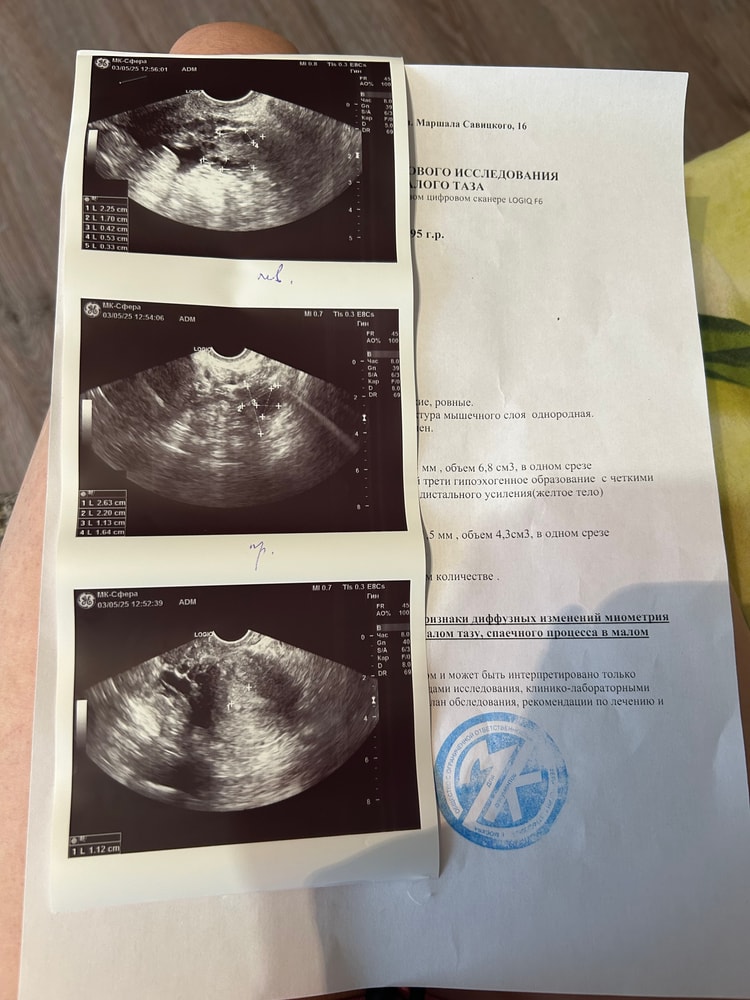

Аня, ой уже 51 дц 🙈🙈🙈🙈

Аня, при цикле 30-33 дня

Дф 12 мм Опять киста функциональная